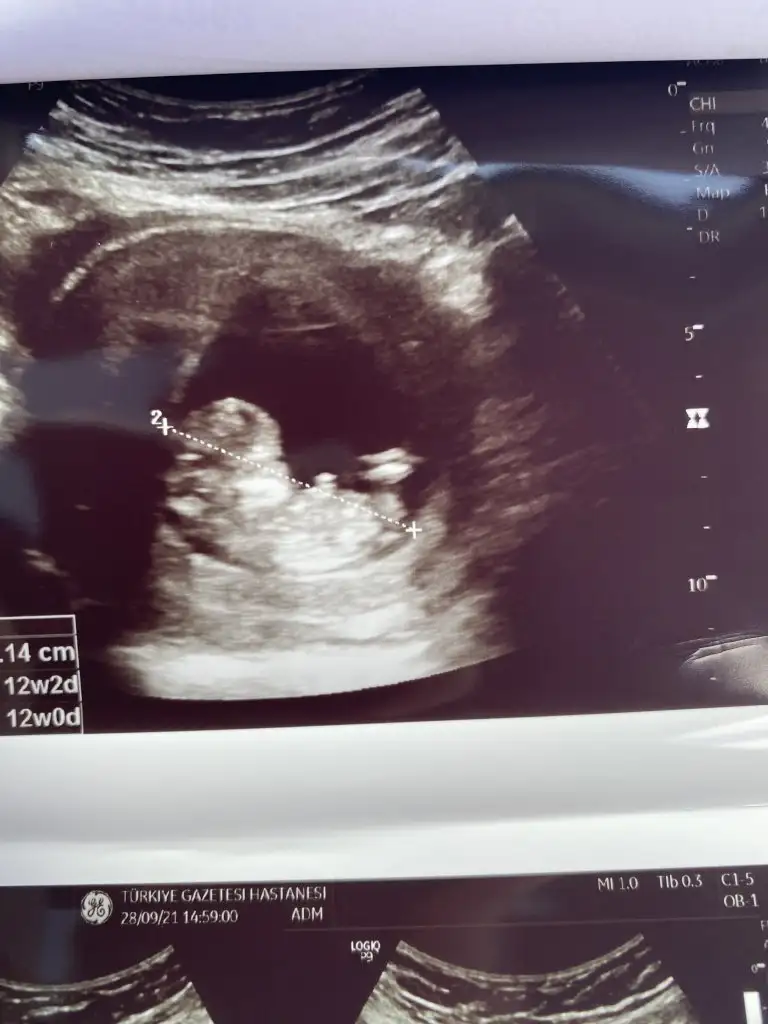

Kız gibi sankiKizlar benim minigimede bakarmisiniz 12+4deyizIkra meyra

Emin olamadım başka USG varsa paylaşın 11 12 13 haftalar olmalıMerhaba rica etsem banada yorum yaparmısınızIkra meyra

Net değil USG başka USG varsa paylaşın emin olamadım kız olabilir sanki SankiKizlar bizde 12+4Bi baksaniz cok mutlu olurumm

malesef baska yokNet değil USG başka USG varsa paylaşın emin olamadım kız olabilir sanki Sanki